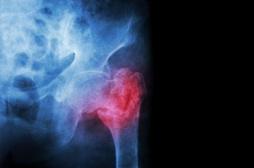

LES MALADIES

J'AI MAL

J ai Mal Bras et mains Bras et mains Tête et cou Torse et haut du dos Jambes et pied